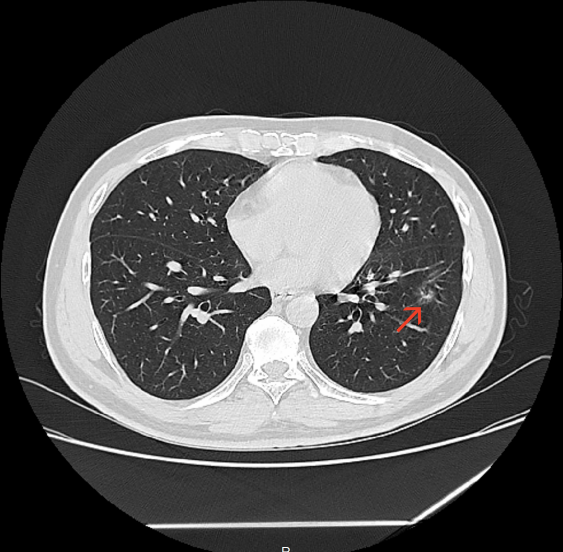

“吴主任,麻烦您给看看,老严是不是和我一样幸运!” 浙大二院解放路院区胸外科吴明主任医师的诊室内今天特别热闹,夏大伯带着他的钓友严大伯前来求医,期望朋友能和自己一样幸运。 事情要回溯到2个月前。年前夏大伯“阳”了一周后,依旧觉得浑身不得劲,来到浙大二院滨江院区做了胸部CT。 不查不知道,一查吓一跳。本来还只是“不得劲”的夏大伯,年三十看到自己的CT报告,当场就感觉四肢无力,呼吸都有些困难了。丰盛的年夜饭,在CT报告“肿瘤不除外”这几个字面前,也变得索然无味。 夏大伯是怎么都在家里待不住了,第二天一大早就再次来到了滨江院区,碰上了过年期间坐诊的胸外科吴明主任医师。 吴明仔细查看了夏大伯的CT,认为这个肺结节看着虽不能完全排除肿瘤,但炎症所致的概率更大。便劝夏大伯放宽心,回去口服抗生素治疗半个月,1个月后再复查胸部CT。 夏大伯“百度”了吴明医生的专家资料后,又听他这么说,悬着的心放下了一半。 待1个月后复查 悬着的另一半心更是彻底放下了 他的肺结节基本消失了 当得知自己的钓友也查出了肺结节,夏大伯二话不说就带着他来到了吴明医生的门诊。 吴明看了严大伯的CT片子,认为虽然他的肺结节中也有炎症成分,但是恶性的可能性也不低。果不其然,经过半个月的抗炎治疗,1个月后严大伯复查了胸部CT,肺结节虽然缩小了,但并未完全消失。 “是不是消炎药不够好?要不要再吃半个月?” “要不要挂盐水?” 严大伯和夏大伯明显还希望通过抗感染治疗,把肺结节治好。 吴明医生告诉他们说,肺结节之间是不同的,需要结合多方面的因素去综合判断。严大伯的这个肺结节恶性的几率还是很高的。 术后,病理果然提示:

根据在胸部CT上的表现,又可将肺结节分为:纯磨玻璃结节、部分实性结节和实性结节。

根据肺结节诊治中国专家共识,在“恶性证据”不十分明显的前提下,目前不建议第一次发现肺结节即马上手术。尤其是一些炎性可能的结节,更是建议经过抗炎治疗后复查,再决定下一步是继续随访还是手术。

同时,也可以选择短期随访,如1-3个月左右复查胸部高分辨率CT,根据结节短期内的变化来决定是否可以延长定期随访的间隔时长。